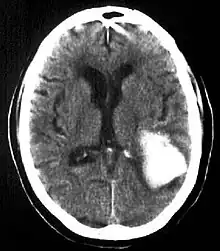

Diagnosis

Computed tomography (CT scan): A CT scan may be normal if it is done soon after the onset of symptoms. A CT scan is the best test to look for bleeding in or around your brain. In some hospitals, a perfusion CT scan may be done to see where the blood is flowing and not flowing in your brain.